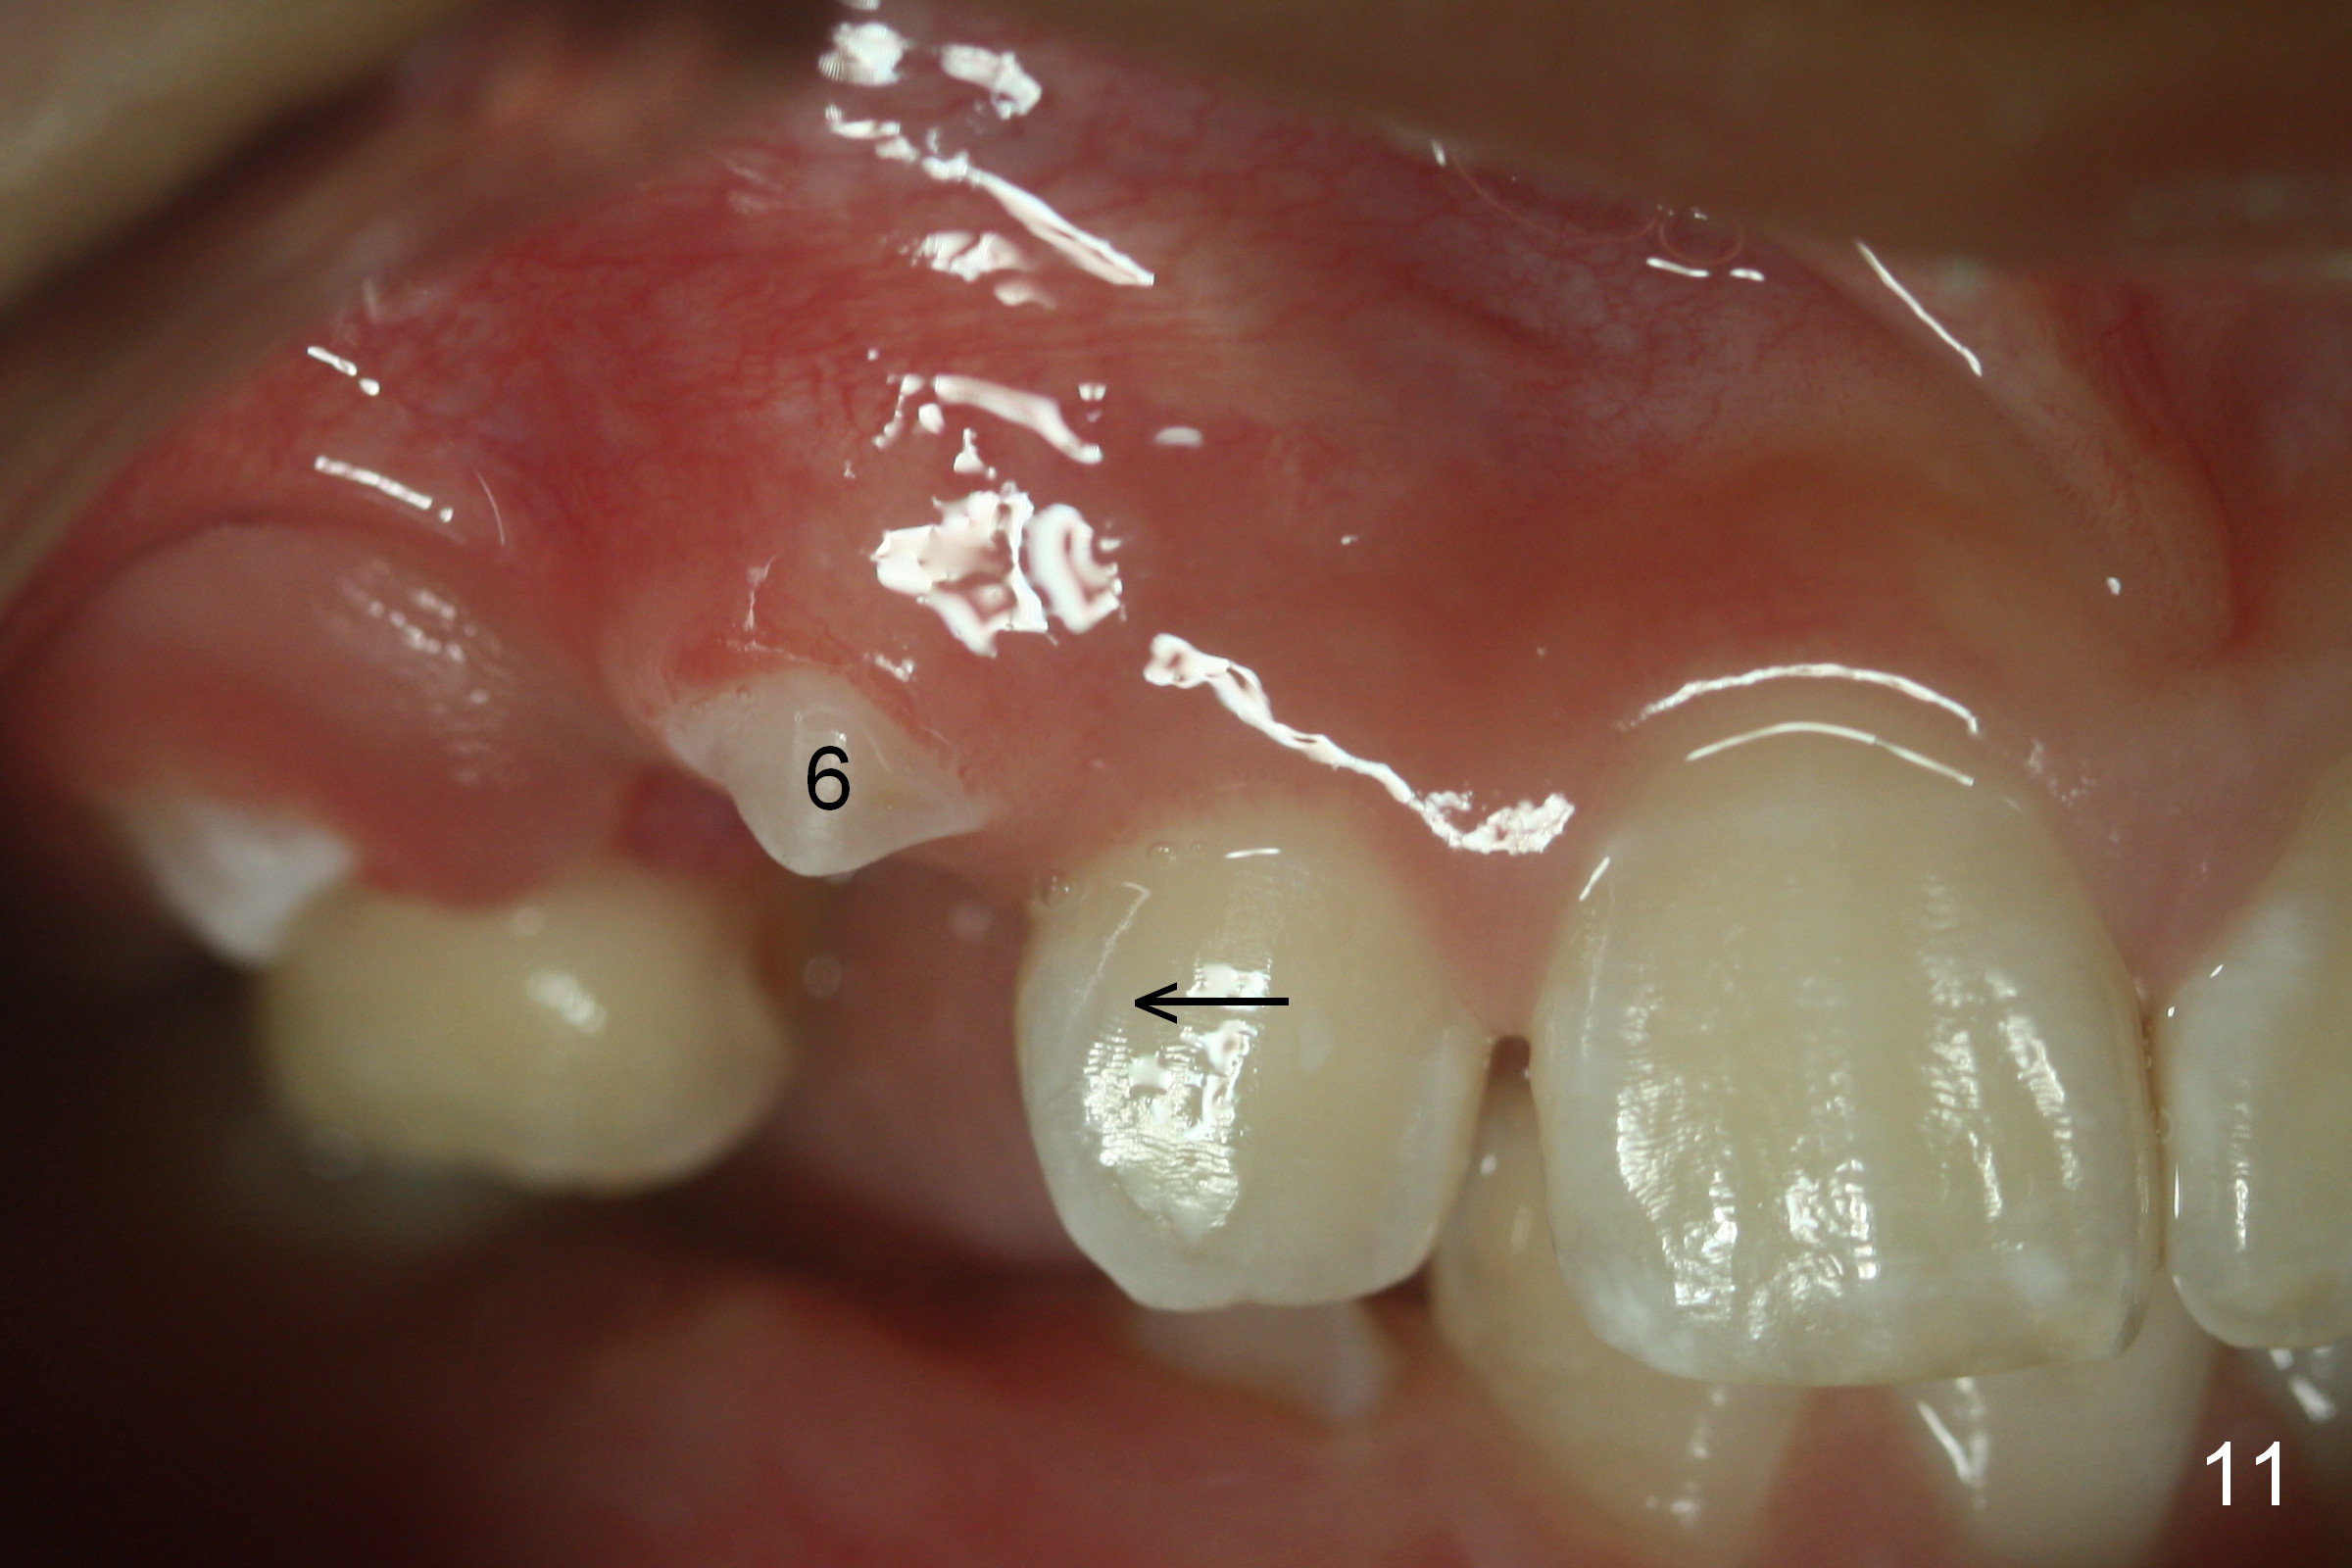

Another 1 month, the teeth #4 and 6 are erupting (Fig.11,12). The tooth A is to be extracted. It is assumed that the diastema between #7 and 8 (due to #7 mesial shift in turn due to #6 erupting, Fig.11 arrow (as compared to Fig.6 <)) will be closed once the tooth #6 erupts fully.